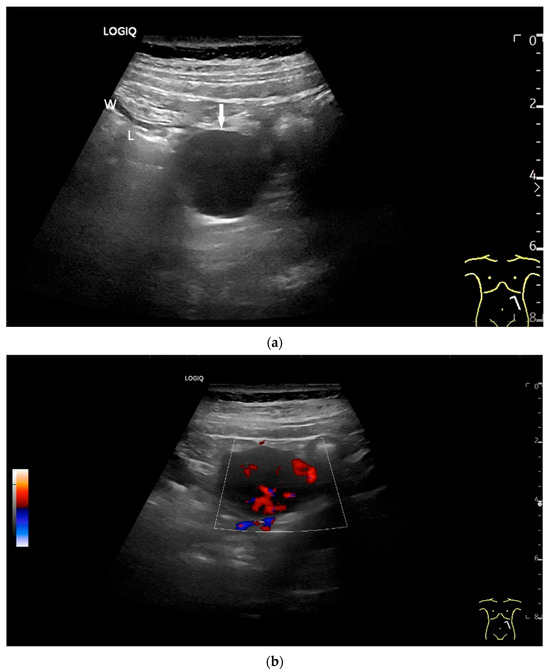

Figure 18.

Small intestine metastasis of a malignant melanoma (between the markers). Significant hypoechoic wall thickening (W) with narrowed lumen reflex (L) and lumen obstruction.

Figure 19.

Small intestine metastasis of pleural mesothelioma. Hypoechoic tumorous wall thickening (T) between the markers. The normal wall with Kerckring’s folds (KF) is visible adjacent to it. Next to the small intestine is a round hypoechoic tumor-suspicious lymph node (L).